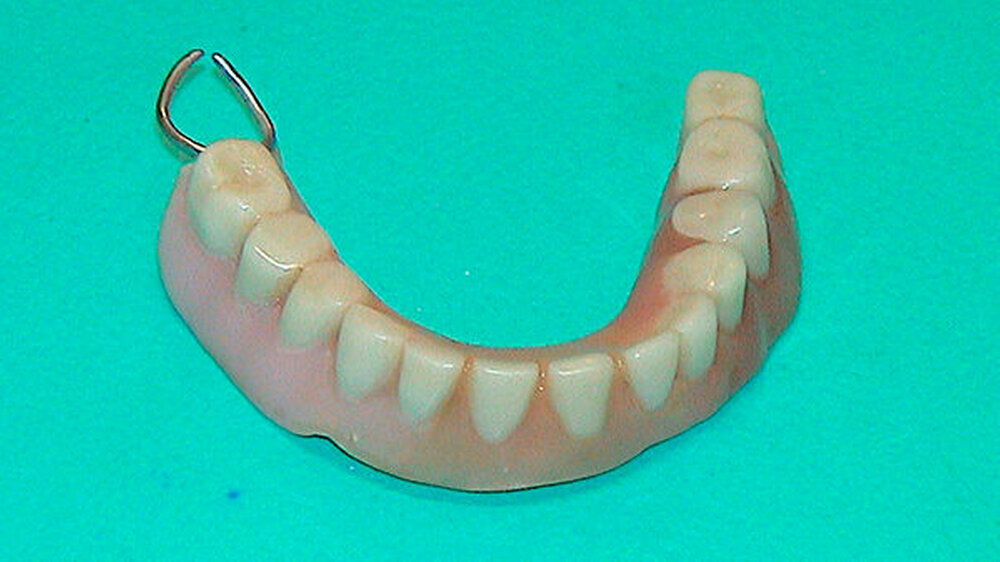

Er schreibt: "Als eine Patientin unsere Praxis aufsuchte, um sich im Notdienst ihre frakturierte totale Oberkieferprothese reparieren zu lassen, so war dies an sich noch kein spektakuläres Ereignis (Abbildung 1). Doch als sie gebeten wurde, auch ihre subtotale Unterkieferprothese mit Drahtklammerfixierung am teil-retinierten Zahn 47 zum Zwecke einer eingehenden Inspektion der Mundhöhle zu entfernen, reagierte sie merkwürdig zögerlich, unwillig und peinlich berührt. Erst nach eindringlicher Bitte gab sie nach und entfernte den Zahnersatz (Abbildung 2).